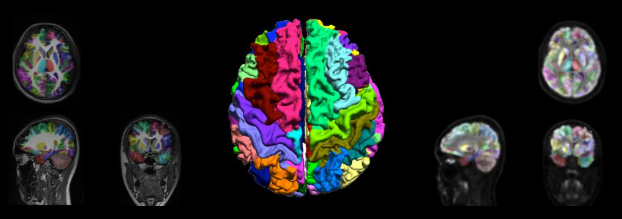

②對于神經系統疾病,PET與MRI圖像能夠提供大腦解剖、生理、代謝與功能方面信息。一體化PET / MR可實現對腦神經系統更精準定位與定量,從分子水平上來揭示人腦生理、病理變化;在腦腫瘤、神經退行性疾病、癲癇等疾病診斷與治療中可發揮重要作用,實現疾病早期診斷(圖3)。

圖3 PET / MR聯合神經腦圖譜分析,精準實現左右腦分區